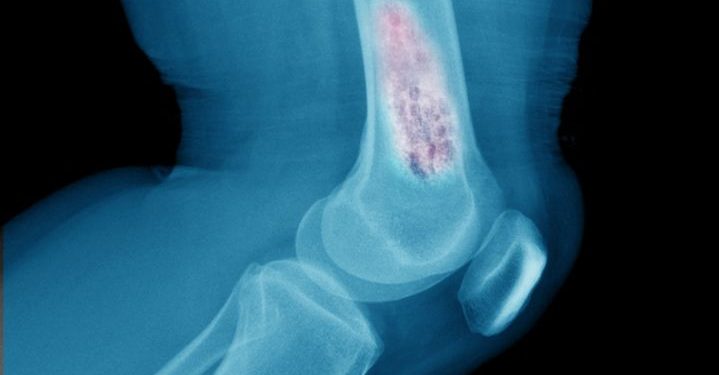

عانى باسم من آلام في الركبة إثر تمزق في الغضروف المفصلي. تم علاجه في المستشفى وبعد الصور ، أوصي بإجراء جراحة تلسكوبية. لكن باسم رفض.